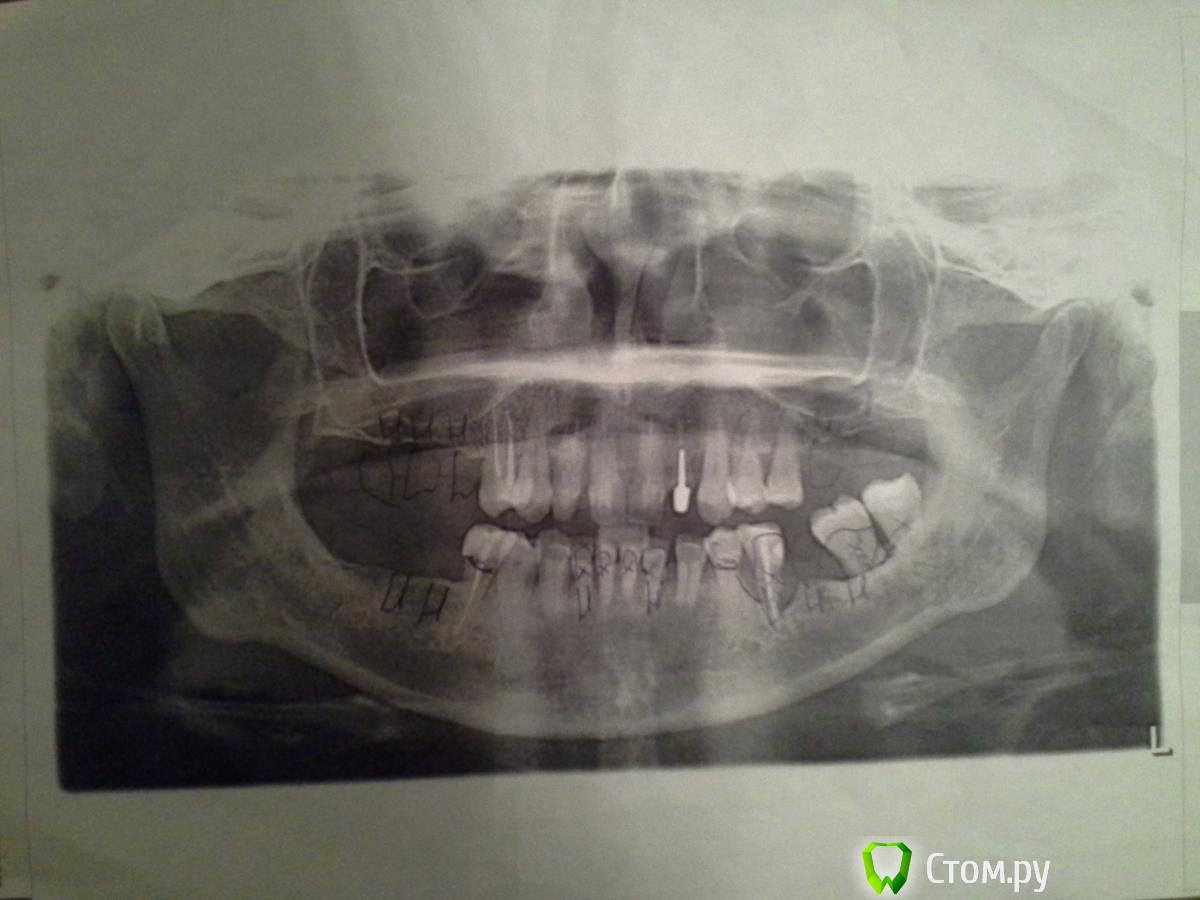

MartyMira Опубликовано 17 января, 2014 Поделиться Опубликовано 17 января, 2014 (изменено) Добрый день, уважаемые специалисты! Важно знать Ваше мнение по имплантации. Сколько имплантатов необходимо в моем случае и возможна ли экспресс (мгновенная) имплантация или базальная (базальтовая) имплантация? Зубы, помеченные крестиками, - удалены. Изменено 17 января, 2014 пользователем MartyMira Ссылка на комментарий

MartyMira Опубликовано 17 января, 2014 Автор Поделиться Опубликовано 17 января, 2014 Еще раз снимок. Ссылка на комментарий

red_butler Опубликовано 17 января, 2014 Поделиться Опубликовано 17 января, 2014 У Вас фото панорамного снимка, напечатанного на простой бумаге, к тому же с рисунками врача. От того что Вы его выложили еще раз, качество лучше не стало. Возьмите снимок в клинике в электронном виде, или сделайте новый. Ссылка на комментарий